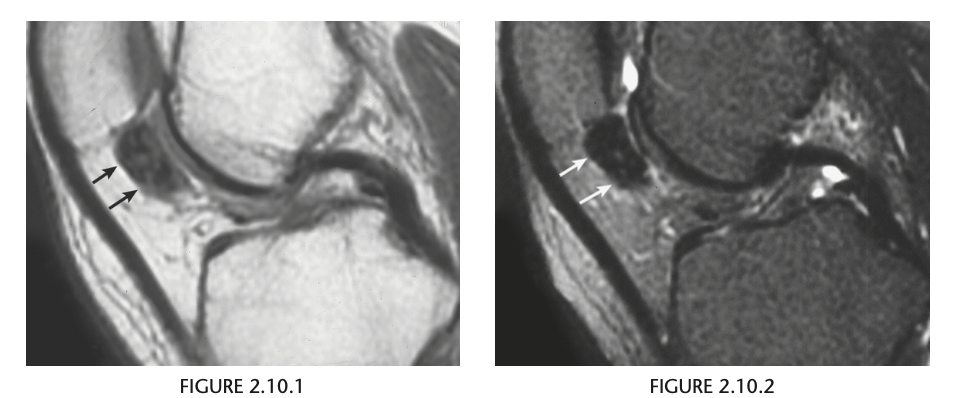

Sagittal proton-density (Fig. 2.14.1)

and fast spin-echo, T2-weighted fat-suppressed

(Fig. 2.14.2) MR images show an area of increased

signal intensity within the anterior cruciate ligament

(ACL), the so-called pseudo-mass (arrows); nonvisual-

ization of the normal ACL fibers; and a joint effusion.

A sagittal fast spin-echo, T2-weighted fat-suppressed

MR image through the lateral joint compartment

(Fig. 2.14.3) shows high-signal-intensity areas in the

subchondral regions of the midportion of the lateral femoral condyle and the posterolateral tibial plateau,

the so-called “kissing contusions”

Full thickness tear of the ACL

MRI features of the torn ACL include an irregular

or wavy contour with decreased angulation on the

sagittal images (i.e., “lying down” or vertically ori-

ented ACL), increased signal intensity on all MRI

sequences in the region of the ACL (i.e., so-called

“pseudo-mass”), posterior displacement of the lateral

meniscus (i.e., “uncovered lateral meniscus” sign),

loss of the normal obtuse curvature with increased

angulation of the posterior cruciate ligament, undu-

lation of the patellar tendon, and the “empty notch”

sign, which is also seen on arthroscopy.

Bone

impaction from transient subluxation results in

the characteristic osseous contusions involving the posterolateral tibial plateau and midportion of the

lateral femoral condyle (i.e., “kissing contusions”).